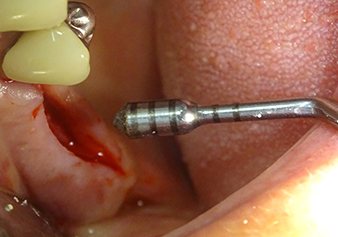

The I2A instrument (diameter 2.0 mm) was then used to perforate the sinus floor intermittently and on the smallest scale possible. This special piezosurgical method ensures that the Schneiderian membrane is not damaged. When the Z25P was used, the membrane was already lifted slightly by the coolant supplied via the instrument tip (Fig. 3). The coolant quantity was just 50% in order to avoid high pressure in the implant bed.

Following an intermediate check (Fig. 4) a further preparation step was performed (Fig. 5). Afterwards, the hydraulic Z35P instrument was used to lift the membrane to the desired position (Fig. 6 and 7). This was followed by further piezosurgical preparation of the implant bed, concluded with a rotary bur and shoulder milling cutter up to the implant diameter of 4.8 mm. Before the implant was inserted, the augmentation material (particle size approx. 0.8-1.6 mm) was introduced underneath the Schneiderian membrane (Fig. 8).